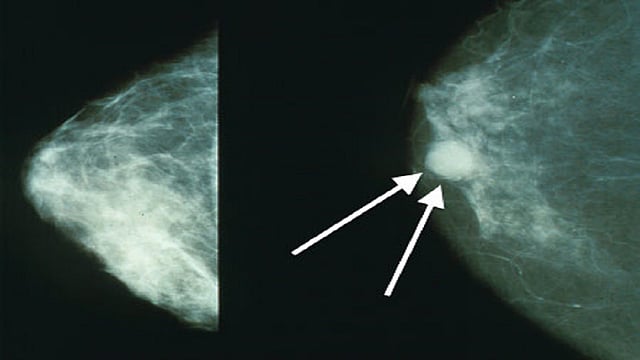

मुंबई  : मुंबईतील परळ येथील टाटा रुग्णालयाने केलेल्या संशोधनानूसार, आता केवळ  3 महिन्यांच्या औषधोपचारांनीच स्तनाचा कर्करोग बरा होऊ शकणार आहे. शिवाय यामुळे औषधोपचारांना लागणारा खर्चही कमी होणार आहे. रुग्णालयाने 11 हजार रुग्णांवर केलेल्या चाचणीतून हा निष्कर्ष काढला आहे. टाटा मेमोरियल रुग्णालयाचे संचालक डॉ. राजेंद्र बडवे, एसीटीआरईसीचे संचालक डॉ. सुदीप गुप्ता आणि टाटा रुग्णालयातील डाॅक्टर गेल्या 15 वर्षांपासून यावर संशोधन करत होते.

ट्रॅस्टुझुमॅब हे औषध स्तन कर्करोगावर प्रभावी मानले जाते. मात्र, यात दोन त्रुटी होत्या. एक तर हे औषध महागडे होते. तसेच, हे औषध वर्षभरासाठी घ्यावे लागत होते. मात्र, टाटा रुग्णायातील डाॅक्टरांनी विकसित केलेल्या नव्या उपचार पद्धतीमुळे हे औषध आता केवळ तीन महिने घ्यावे लागणार आहे, असे रुग्णालयाचे संचालक डाॅ. राजेंद्र बडवे यांनी सांगितले.

या औषधाच्या मूळ ब्रँडची किंमत 8 ते 10 लाख रुपये असुन ते सर्वसामान्यांना न परवडणारे आहे. शिवाय वर्षभर औषध घेतल्याने हृदयावरही त्याचे विपरित परिणाम होते.  या कारणांमुळे गेल्या पंधरा वर्षांपासून उपचाराचा कालावधी कमी करण्यावर संशोधन सुरु होते. अखेर टाटा मेमोरियल रुग्णालयाच्या डॉ. सुदीप गुप्ता यांच्या मार्गदर्शनाखाली सुरू असलेल्या संशोधनाला यश आल्याचे डाॅ. बडवे म्हणाले.  भारतीय महिलांमध्ये ' एचइआर 2' या प्रकारातील स्तनाचा कर्करोग सर्रास आढळून येतो. अशा महिलांंना या दोन्ही गोष्टींमुळे मोठा दिलासा मिळणार असल्याचेही ते म्हणाले.

नवी उपचार पद्धती तीन महिन्यांचीच असल्याने स्तन कर्करोगावरील ट्रॅस्टुझुमॅब  हे औषध सर्वसामान्यांना खरेदी करता येऊ शकेल. त्याचा मोठा फायदा त्यांना होईल. या अभ्यासातून हृदयावरही जास्त विपरीत परिणाम झाल्याचे आढळले नाही, असे एसीटीआरईसीचे संचालक डॉ. सुदीप गुप्ता यांनी सांगितले आहे.

आम्ही स्तनाच्या कर्करोगाबाबत अभ्यास करत होतो. त्याची उपचार पद्धती कशी कमी करता येईल यावर संशोधन सुरु होते. मात्र, आता नव्याने समोर आलेल्या उपचार पद्धतीमुळे एका वर्षांचा कालावधी थेट 3 महिन्यांवर आला आहे. एचइआर 2 हा स्तनाचा कर्करोग देशातील 25 टक्के लोकांमध्ये आढळतो.